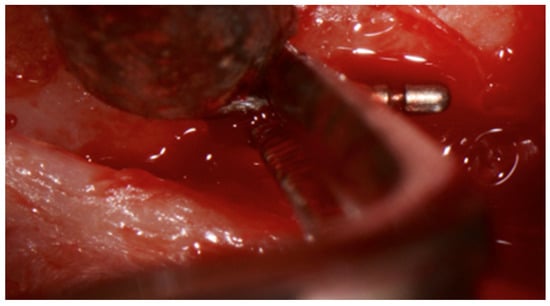

In December 2019, region 45 was operated and the fractured instrument tip removed (Figure 5 and Figure 6).

Figure 5.

In situ image showing the removal of the broken periodontal probe tip from buccal, which was removed with pliers after careful luxation.